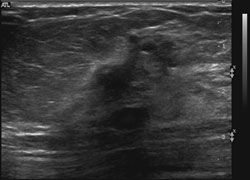

Ultrasound demonstrates a dominant spiculated and irregular hypoechoic mass

Ultrasound demonstrates a dominant spiculated and irregular hypoechoic mass with dense posterior shadowing (known cancer). There were adjacent, similar-appearing hypoechoic irregular, spiculated masses present also.